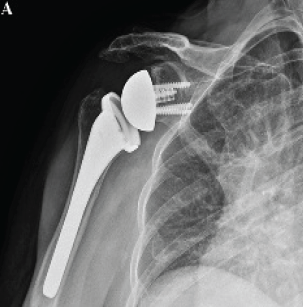

Strength Recovery with Lateralized Reverse Total Shoulder Arthroplasty Combined with Pectoralis Major Transfer for Rotator Cuff Arthropathy with Internal Rotational Deficiency: A Case Report

Chang Hee Baek , Bo Taek Kim , Jung Gon Kim

………………………………p.97-103